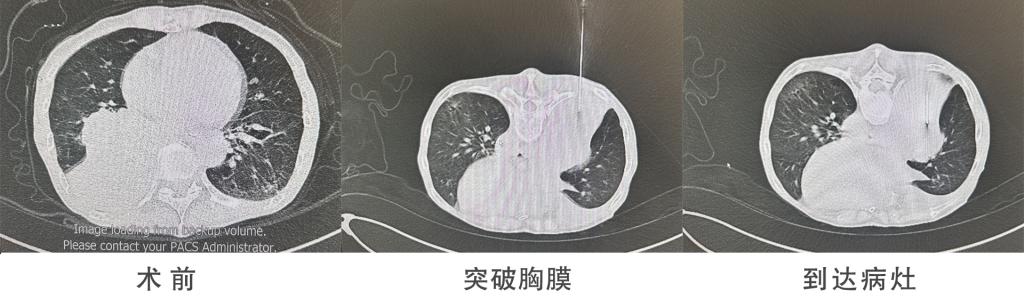

术前,团队通过三维重建技术对患者影像资料进行深度分析,精准规划穿刺路径,避开血管、支气管等重要脏器,最大限度降低手术风险;术中,在CT实时导航引导下,医生手持细如笔芯的穿刺针,如同“精准导航”般直达病灶,成功获取足量组织样本;术后,样本即刻送往病理科检测,患者仅需局部按压止血,4小时后即可下床活动。